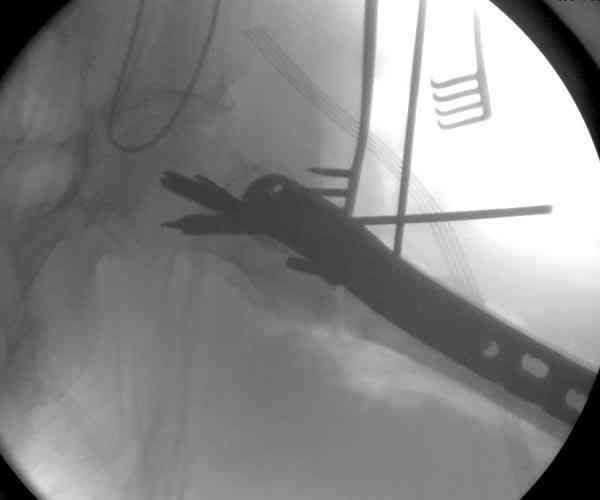

Адекватная фиксация достигается длинным 95 градусным Blade Plate, где

клинок пластины, связывая головку со средней трети бедра, создал бы

условия для сращения.

Другой вариант пластины, это Synthes Proximal Locking Plate

предназначенный для лечения прксимальных переломов бедра, где три

шурупа: два 7.3 мм, введенных в головку под углом 95, 120 и 5.0 мм в

130 градусов, создают угловую стабильность.

Профилактику прорезывания шурупов в кости можно добиться введением в

отверстие цемента, потом проведением шурупа, цемент, застывая,

удерживает шуруп в правильном положении.